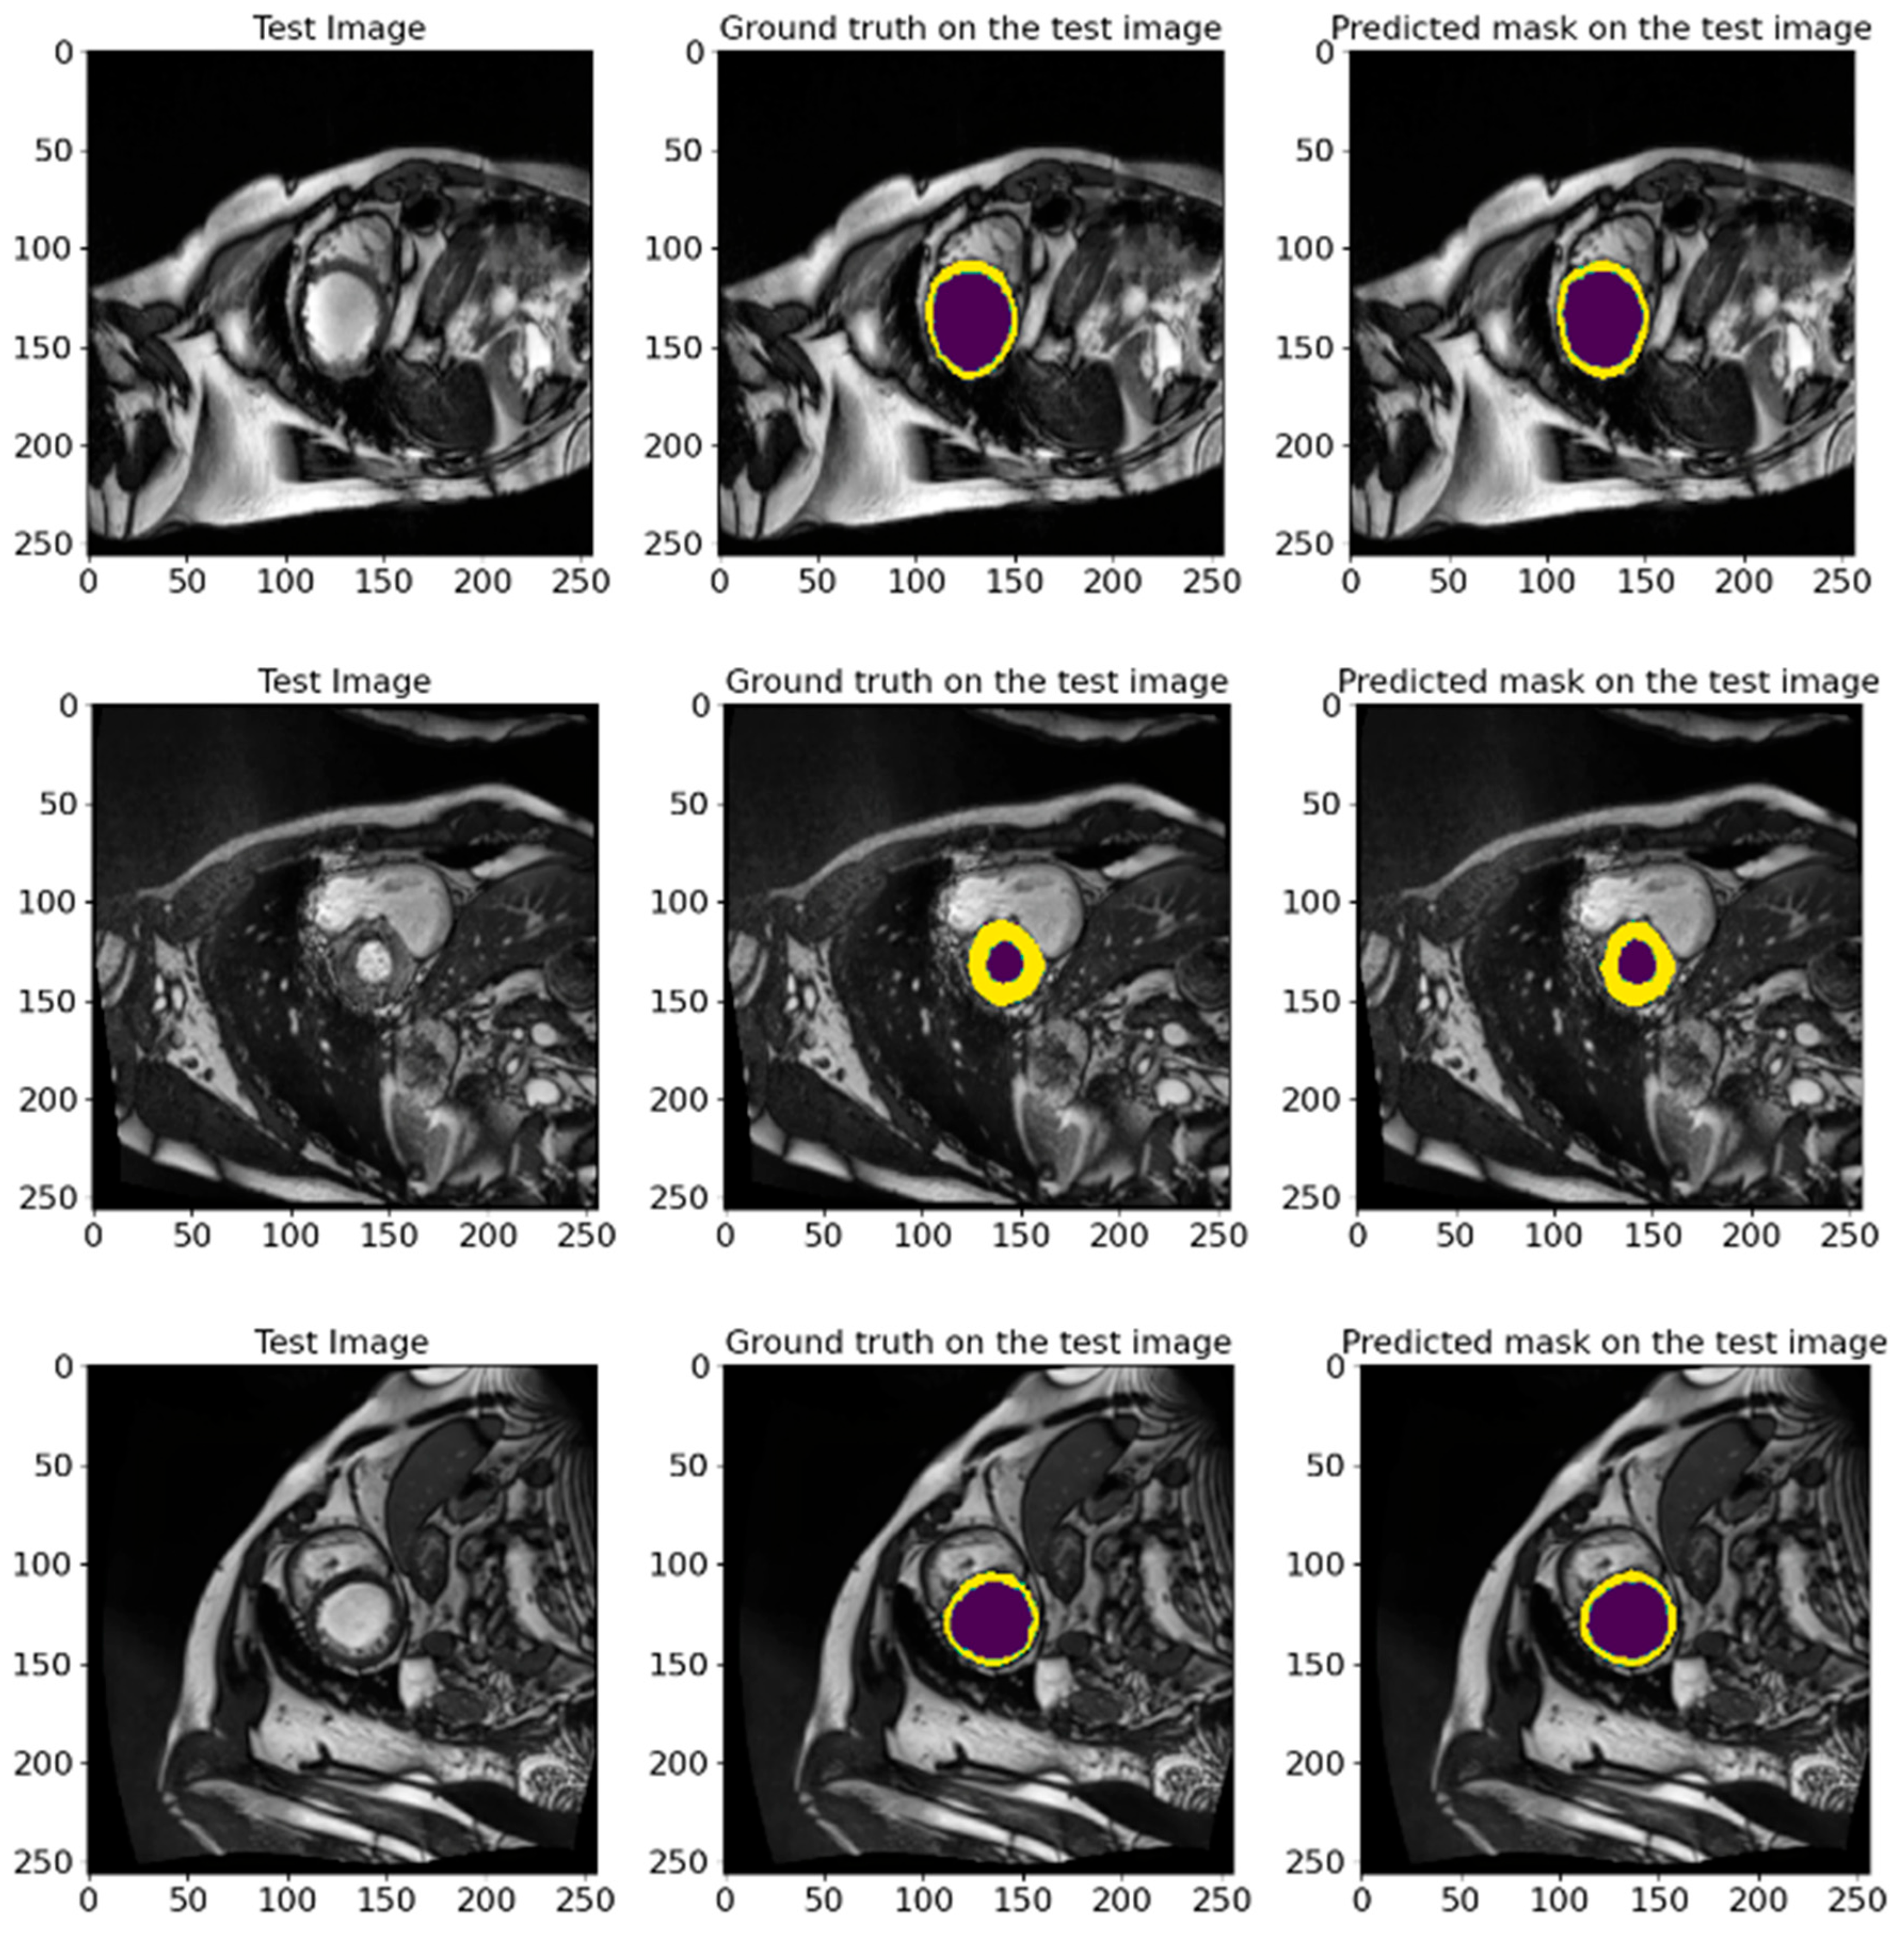

4.3. The Performance of the Proposed Model

4.4. Comparison with Other State-of-the-Art Models